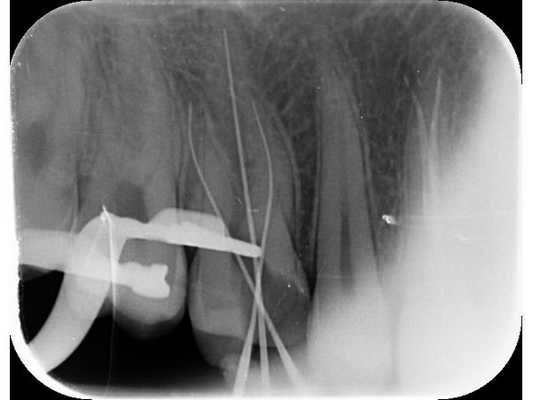

- Определение рабочей длины корневых каналов при помощи системы К-файлов и апекслокатора (прибора, который измеряет длину корневого канала).

- Контроль рабочей длины при помощи визиографа.